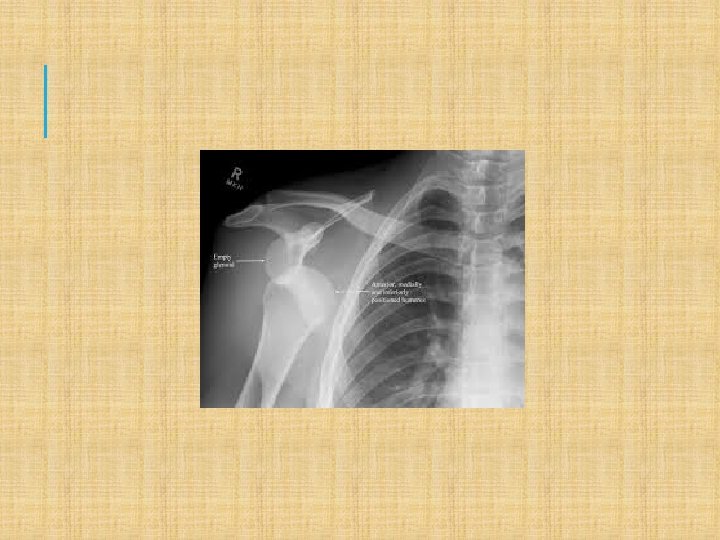

XRAY FOR DIAGNOSIS

3) Shoulder Subluxation/dislocation Mech-Forceful fall, clothesline, susceptible when in ER and ABD Symp- obv def, intense pain, loss of ROM, possible numbness Tx- Reduction (pain relief and muscle relaxer) immobilize and rehab strengthen whole area to stop recurrent ones Subluxation- comes out and goes back in OR only partially out of socket